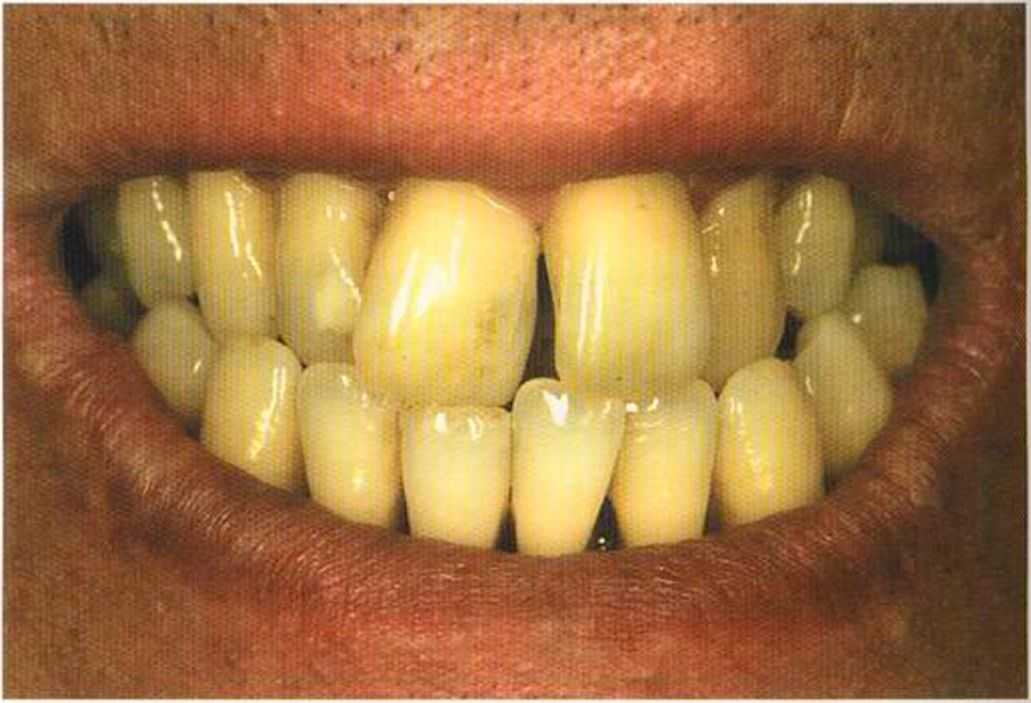

Этот пациент — португалец. Он всю жизнь имел такое положение зубов. Небнорасположенный боковой резец теперь необходимо удалить, а затем воссоздать как эстетику, так и функцию в области фронтальной группы зубов. Планируется изготовить коронки In-Ceram в области 11 и 21 и соединить их вместе из-за увеличивающейся подвижности зубов.

Препарирование, проводимое доктором Риссе, оценивается как очень сложное. Режущие края центральных резцов сильно дивергируют, что создает неудобство при формировании хорошего уступа.

Из-за сильной протрузии центральных резцов на них всегда падает итого света, и они кажутся очень большими. Чтобы смягчить этот эффект, мы выбрали более темный цвет для реставрации.

Готовая работа привела в восторг нашего пациента. Он даже не мог себе представить, что соединенные вместе коронки могут выглядеть так естественно. Мы решили не копировать на реставрацию белое пятно, имеющееся на 12 зубе.